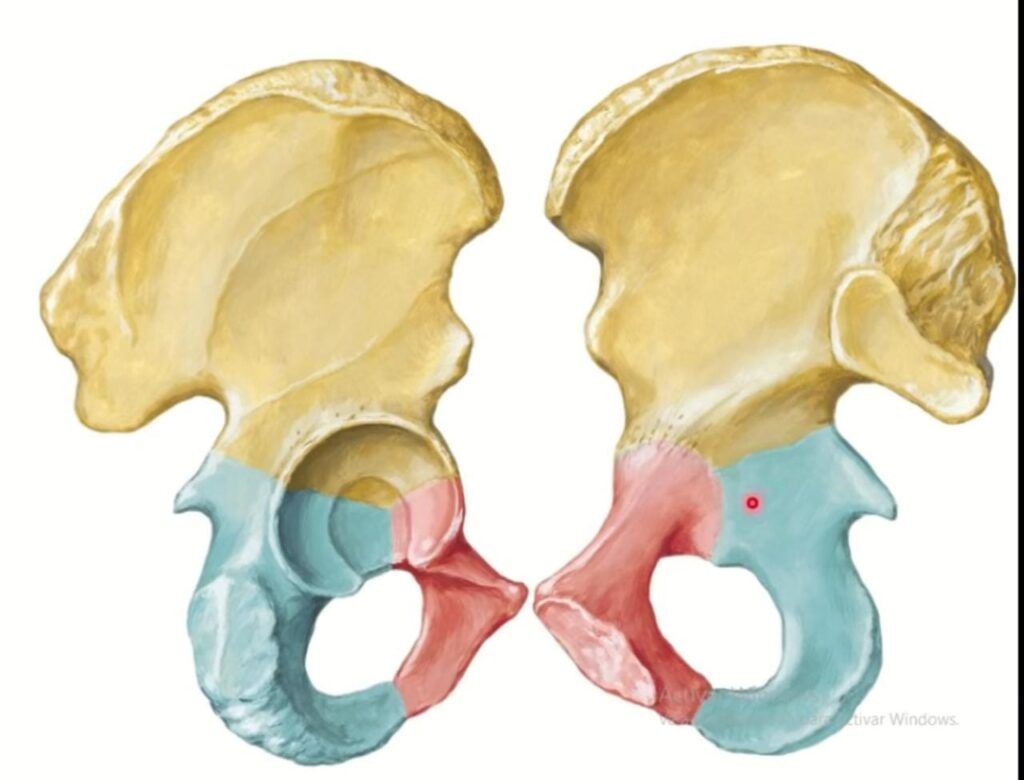

Los huesos coxales, también conocidos como huesos de la cadera, son un par de huesos grandes y fuertes que se encuentran en los lados de la pelvis. Cada hueso coxal está compuesto por tres huesos fusionados: el ilion, el isquion y el pubis. Estos huesos se articulan entre sí en el acetábulo, formando la articulación de la cadera.

El sacro y el cóccix son huesos que se encuentran en la parte posterior de la pelvis, debajo de los huesos coxales. El sacro es un hueso triangular formado por la fusión de cinco vértebras sacras. Se encuentra en la parte superior del cóccix y se une con los huesos coxales. El cóccix, por su parte, es un pequeño hueso en forma de triángulo compuesto por la fusión de varias vértebras rudimentarias.